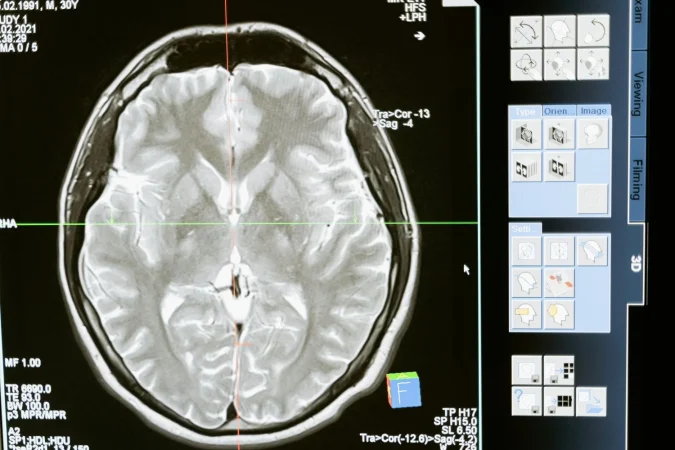

A los 10 años, Natasha Demakina, quien nació en Saransk, Rusia, notó algo inusual: podía ver dentro de los cuerpos de las personas. Ella afirmó que su percepción le permitió identificar dolencias internas como órganos, huesos y tumores, que solo son detectables con la tecnología médica moderna, como radiografías o resonancias magnéticas, de modo que siempre tuvo superpoderes.

La comunidad científica fue cautivada por este episodio y sometió a esta mujer a varias pruebas para determinar si realmente tenía poderes sobrenaturales o si era solo un truco, resultado de lo cual, llegaron a la conclusión de que los poderes de ojos de rayos X de esta mujer no podían ser explicados por la ciencia convencional, así que era necesario recurrir a explicaciones alternativas.